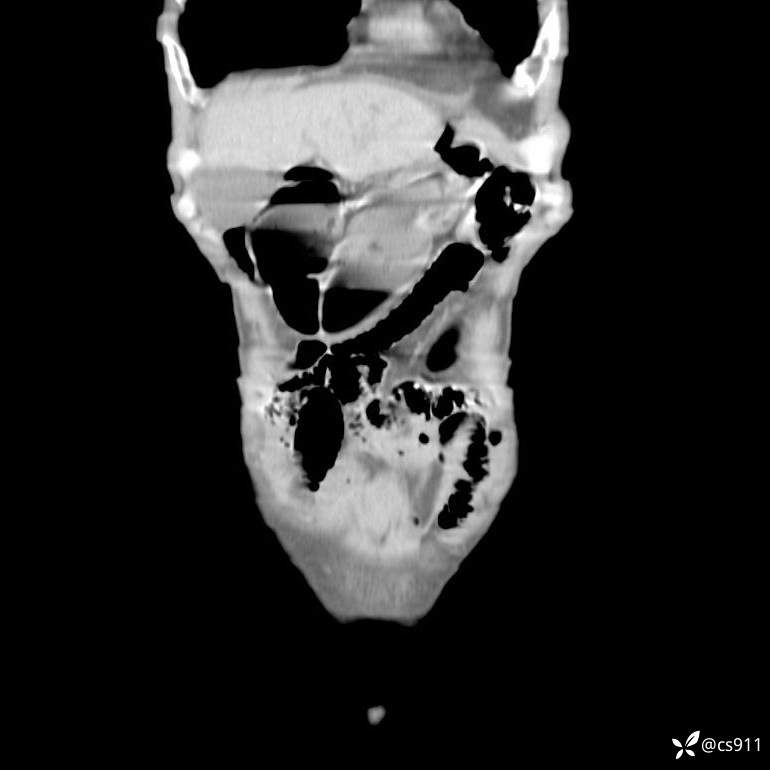

急腹症之急诊CT,原因?答案公布

男,77岁,腹痛、腹胀伴恶心呕吐1天。呕吐胃内容物,非喷射性呕吐,有咖啡色样胃内容物,诉有胃穿孔病史。查体:全腹平,下腹部压痛,全腹无反跳痛,叩诊呈浊音,移动性浊音阴性,肠鸣音减弱,1-2次/分。肛检:直肠未扪及明显肿物,可触及大量粪块。

T 36.6℃ P 80次/分 R 26次/分 BP 100/60mmHg

白细胞(WBC) H 14.55 10e9/L 4-10

中性粒细胞百分率(NEUT%) H 85.7 % 40-75

血淀粉酶(AMY) HH 1859 U/L 35-135

癌胚抗原(CEA) H 27.44 ng/ml 0-5

呕吐物 潜血试验 * 阳性 阴性

患者轮椅入室检查神志清楚, 能配合摆位和呼吸